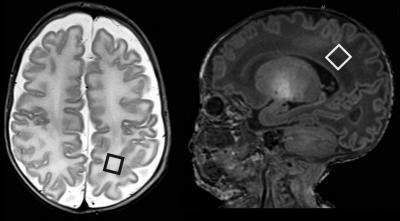

Axial T2-weighted (left) and sagittal T1-weighted (right) MR images show position and orientationof posterior white matter point-resolved spectroscopy voxel.

(Photo Credit: Radiological Society of North America)